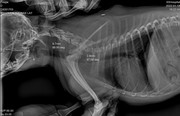

Коллапс трахеи форум